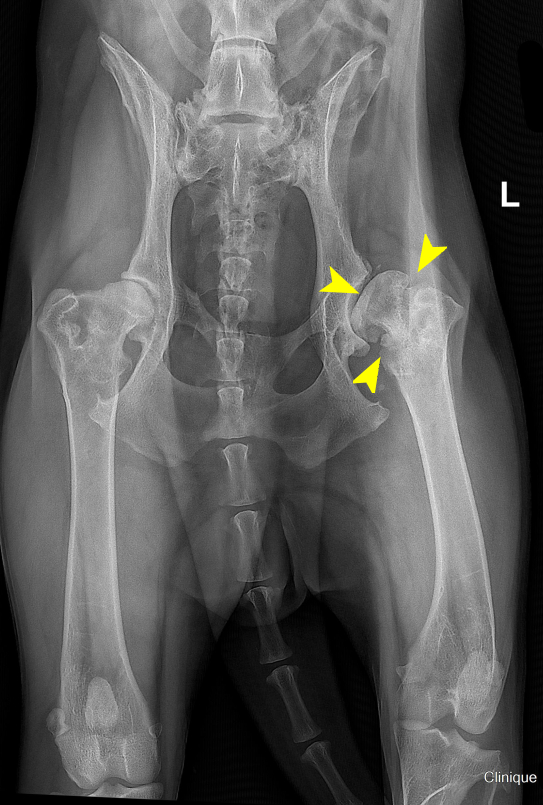

Radiographie de hanches chez un Berger Allemand de 5 ans présentant une coxarthrose bilatérale sévère, marquée à gauche par une déformation importante de la tête et du col fémoral, ainsi qu’une arthrose avancée.